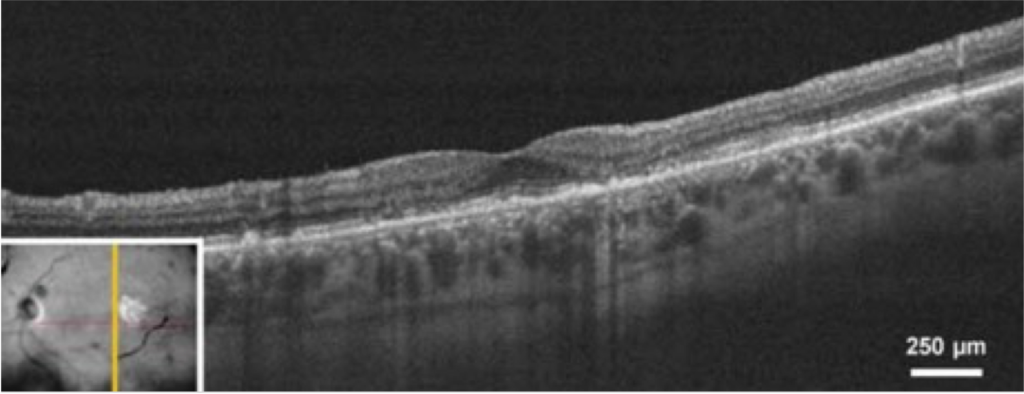

Tomografia de coerência óptica (OCT)

A OCT é uma técnica importante de imagem para diagnosticar e monitorar a DMRI. Este método envolve tirar fotos transversais da retina para fornecer um panorama de saúde detalhado.7,8